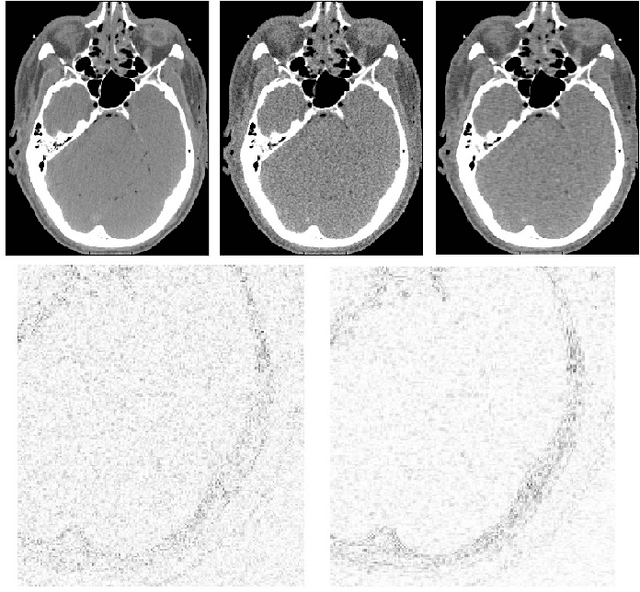

Abstract:We propose a supervised machine learning approach for boosting existing signal and image recovery methods and demonstrate its efficacy on example of image reconstruction in computed tomography. Our technique is based on a local nonlinear fusion of several image estimates, all obtained by applying a chosen reconstruction algorithm with different values of its control parameters. Usually such output images have different bias/variance trade-off. The fusion of the images is performed by feed-forward neural network trained on a set of known examples. Numerical experiments show an improvement in reconstruction quality relatively to existing direct and iterative reconstruction methods.

Abstract:We propose a direct reconstruction algorithm for Computed Tomography, based on a local fusion of a few preliminary image estimates by means of a non-linear fusion rule. One such rule is based on a signal denoising technique which is spatially adaptive to the unknown local smoothness. Another, more powerful fusion rule, is based on a neural network trained off-line with a high-quality training set of images. Two types of linear reconstruction algorithms for the preliminary images are employed for two different reconstruction tasks. For an entire image reconstruction from full projection data, the proposed scheme uses a sequence of Filtered Back-Projection algorithms with a gradually growing cut-off frequency. To recover a Region Of Interest only from local projections, statistically-trained linear reconstruction algorithms are employed. Numerical experiments display the improvement in reconstruction quality when compared to linear reconstruction algorithms.